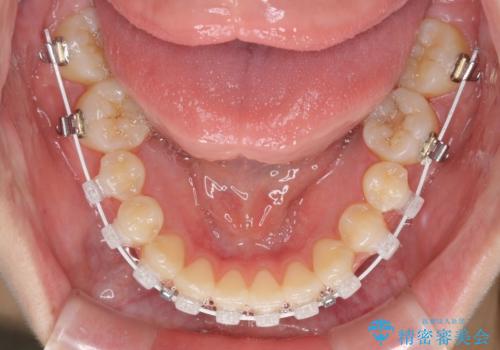

- 矯正装置

- 審美装置

オープンバイトの原因は舌の突出癖であり、癖が改善されないと治療経過に影響を及ぼすため、舌のトレーニングを指示しました。

なかなか癖が改善されず、トレーニングも断続的に行ったため、治療期間は長期化しました。